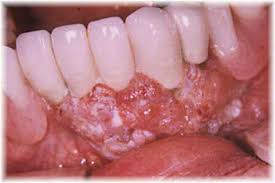

Tobacco can affect youth activities and athletic performance. Tobacco narrows blood vessels and puts a strain on the heart, it also leads to lack of oxygen and shortness of breath. Smokers run slower and can't run as far as nonsmokers.The Environmental Protection Agency has concluded that secondhand smoke causes lung cancer in adults and greatly increases the risk of respiratory illnesses in children and sudden infant death syndrome. The carbon monoxide in tobacco smoke increases the chance of cardiovascular diseases, and children who breathe secondhand smoke are more likely to develop ear infections, allergies, bronchitis, pneumonia, and asthma. Older children whose parents smoke get sick more often.